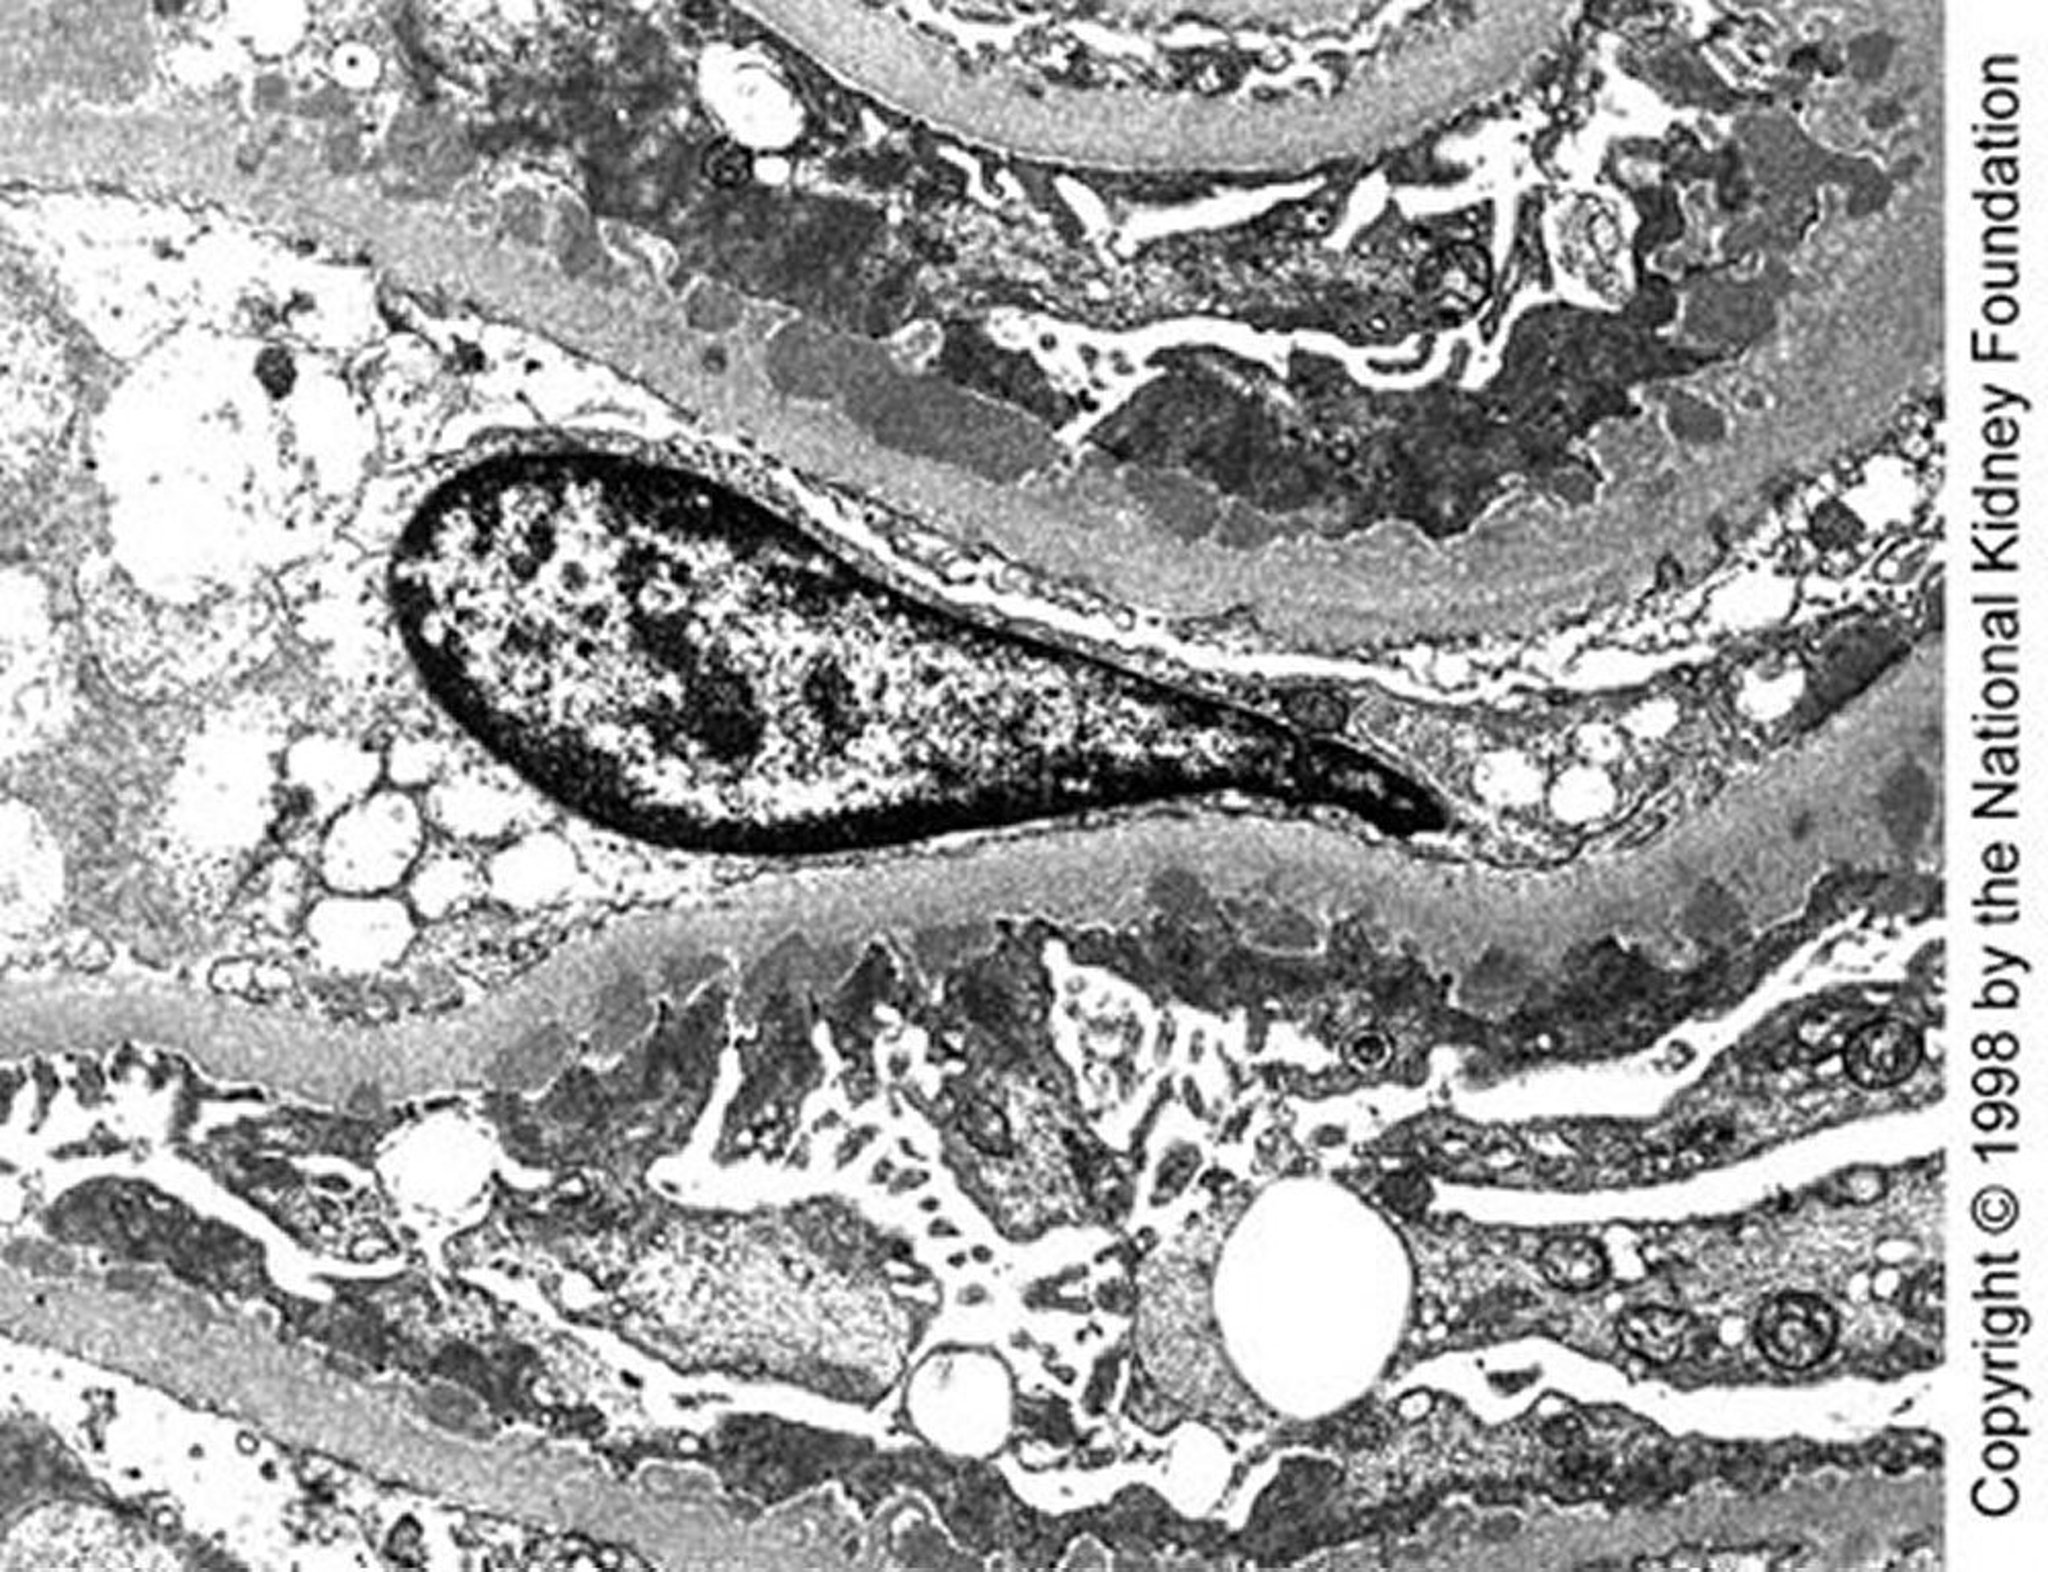

Membranöse Nephropathie (dichte Ablagerungen)

Mittelgroße, dichte subepitheliale Ablagerungen sind in der Transmissionselektronenmikroskopie im späten Stadium I der Krankheit zu sehen (×10.200).

Image provided by Agnes Fogo, MD, and the American Journal of Kidney Diseases' Atlas of Renal Pathology (see www.ajkd.org).